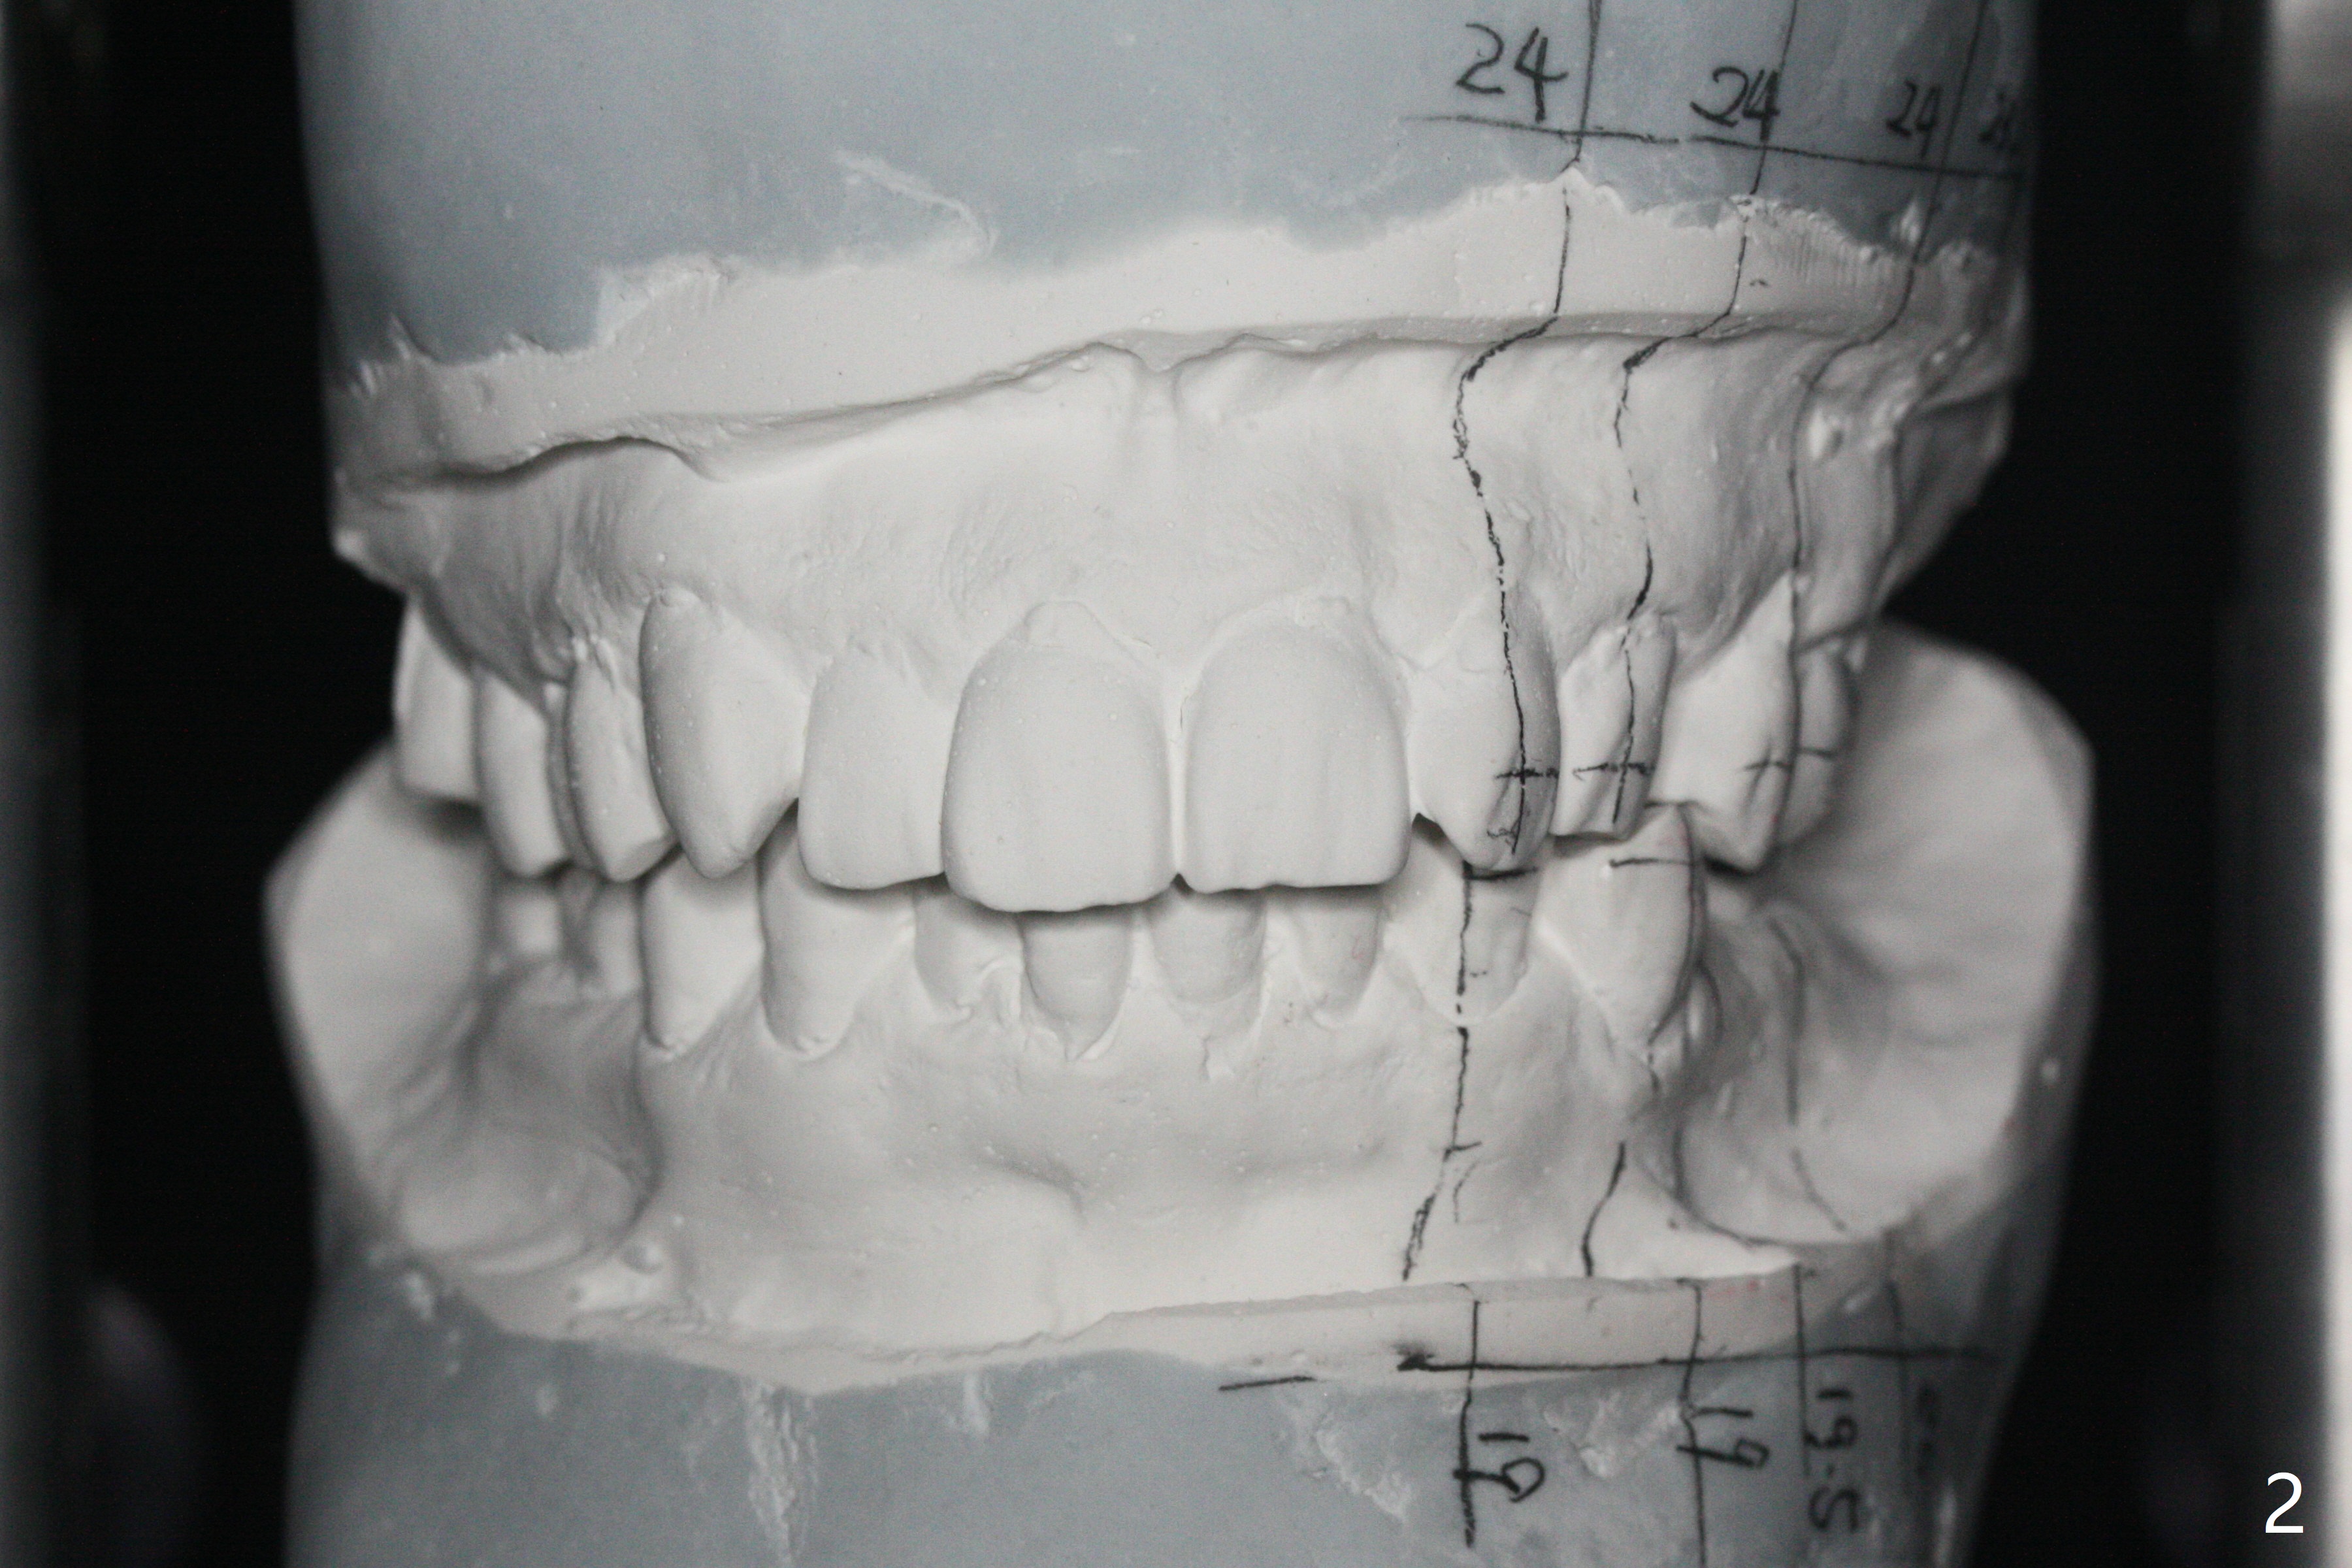

A 54-year-old man remains difficult in mastication in spite of implant placement at #14 and 31 (Fig. A, B, E, including screw loosening (poor trajectory at #14)). In addition to 2 more implants at #15 and 18 with guide, malocclusion seems to be necessary to be addressed (Fig.1-5). It appears that UR, LL4 should be extracted for orthodontic treatment (Fig.6-10). To reduce screw loosening, IS guide will be used to place IBS (5x9mm) and tissue-level (5x11mm) implants at #15 (PRF)and 18, respectively. If the one at #14 or 15 keeps loosening, splint #14 and 15 crowns. In fact the patient agrees with limited ortho (UR7 cross bite).